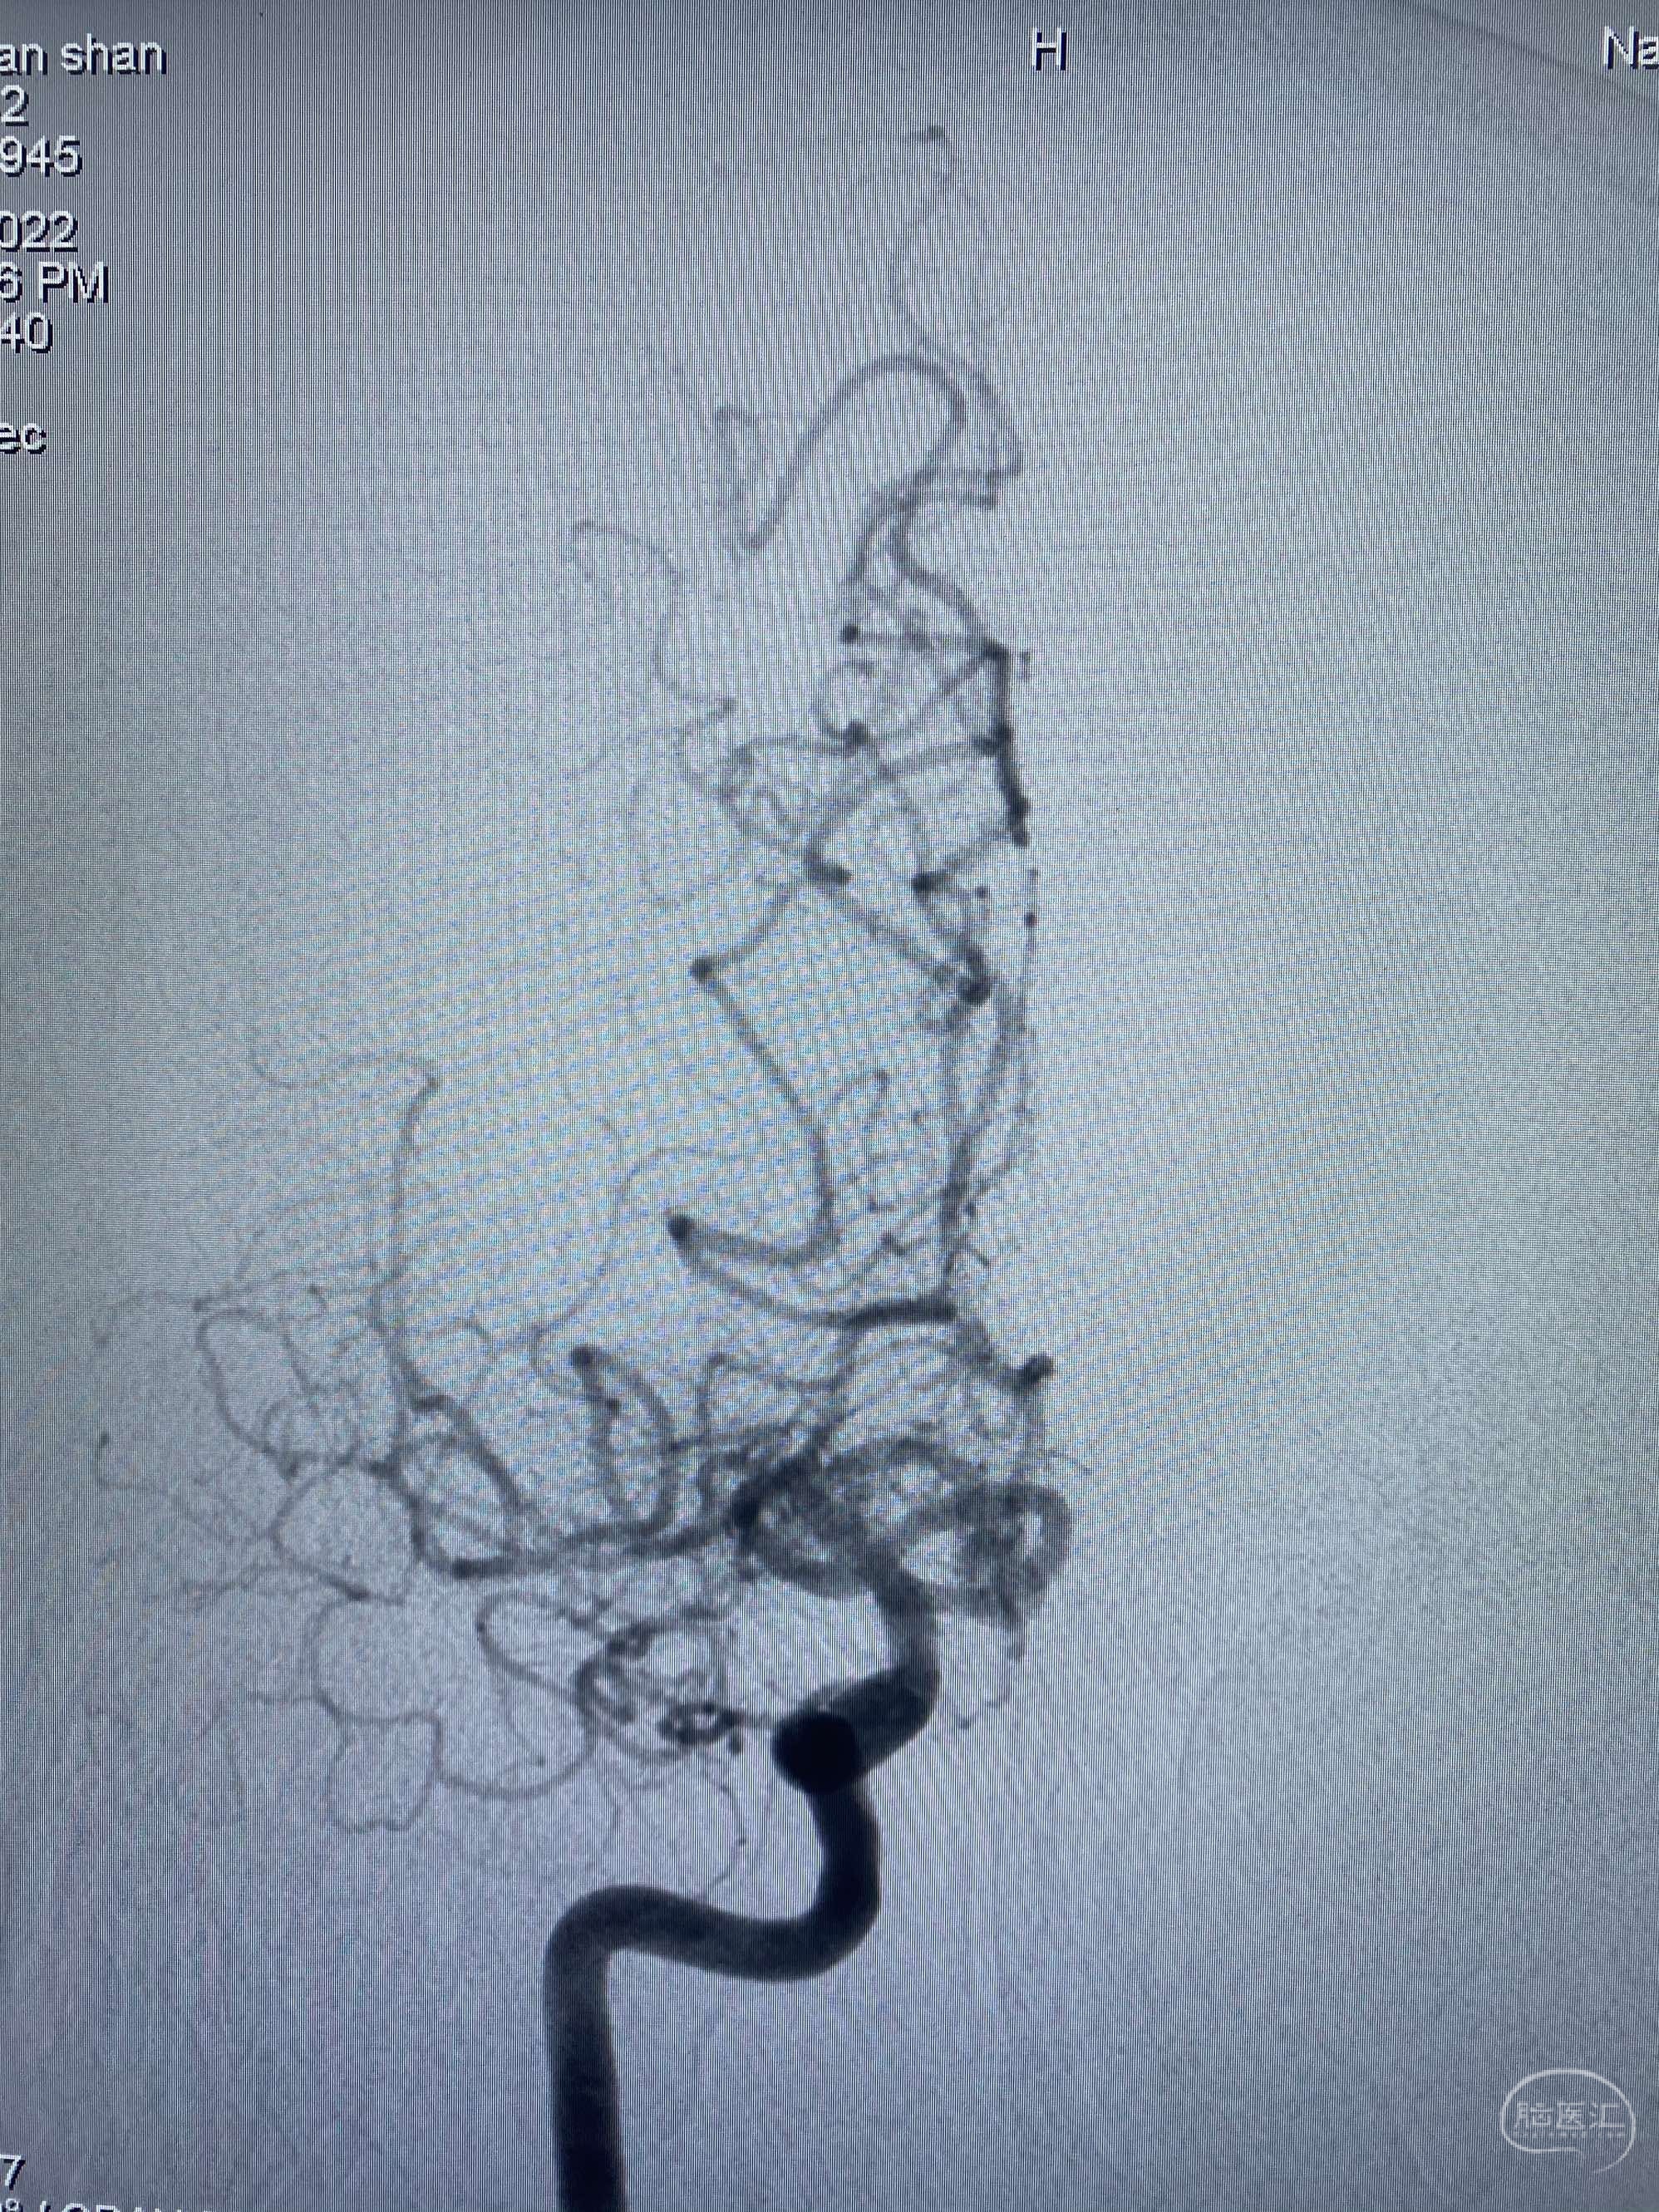

MLS,M79Y,sah,双侧MCA烟雾病,Heubner返动脉瘤,前交通段开窗,细支发出Heubner返动脉,瘤颈细长,瘤颈口比微导管细,弹簧圈2mmx3cm“隔山打牛”填塞治愈,Heubner返动脉保留。

Heubner返动脉是由大脑前动脉A1末端发出的豆纹动脉,由于走形和A1段相反,故称Heubner返动脉,该动脉梗塞可能引起尾状核头梗塞,引起偏瘫和面瘫,便身震颤等症状。